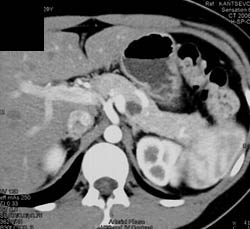

Pseudocyst With Septation